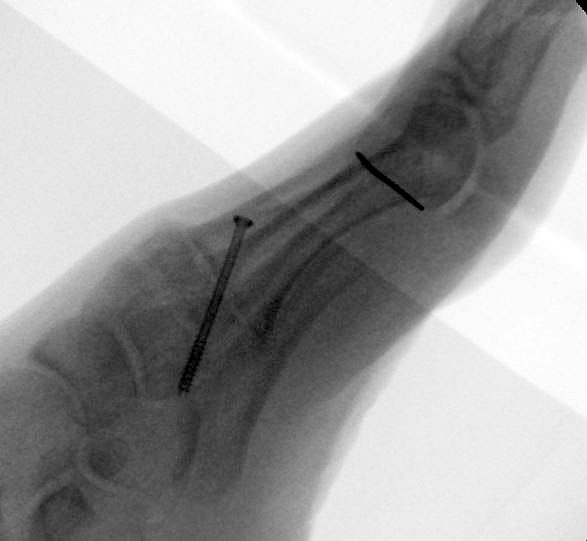

Es wird hier die Lapidusarthrodese mit Fixation durch eine medial angebrachte winkelstabile Platte in Kombination mit einer Zugschraube beschrieben 2. Durch diese Kombination läßt sich eine verglichen zur Schraubenosteosynthese hohe Primärstabilität erreichen, verbunden mit einem niedrigen Risiko einer Pseudarthrosenbildung 3.

Operationstechnik

Direkt postoperativ Röntgenkontrolle (Fuß in zwei Ebenen). Sechs Wochen postoperative Röntgenverlaufskontrolle in zwei Ebenen im Stehen. Ist die Überbauung der Arthrodese nicht gut zu beurteilen, kann eine ergänzende 45° Supinationsaufnahme des Fußes angefertigt werden, die einen guten Einblick in das Tarsometatarsale-I-Gelenk ermöglicht.